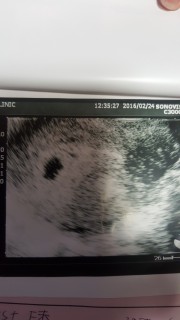

双子ちゃんです。 それぞれ7.3㎜、7.0㎜です。 しっかり元気に育ってくれることを願うばかり(^人^)